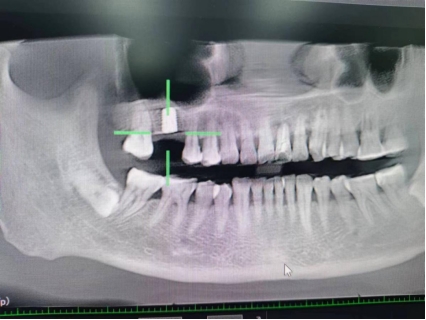

王先生术前检查图

第一台手术结束后,预约已久的王先生也在下午进行种植牙手术,据了解,在朋友的推荐下,王先生已提前完成各项检查等待手术,种植手术结束后,王先生说:“伤口没什么不适感觉,也没有感觉肿胀疼痛”。